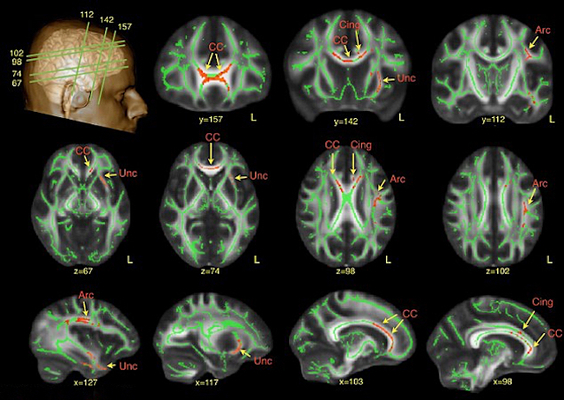

Cada uno de estos diferentes tipos de información se procesan en diferentes partes del cerebro, por lo que el sistema CMU puede elegir la categoría general de lo que está en la mente de una persona. Para probar su destreza, los investigadores hicieron que siete participantes leyeran las frases, registrando los patrones de activación cerebral que les acompañaban. Después de entrenar el algoritmo en 239 de las frases y los escáneres coincidentes, fue capaz de componer la última oración basándose únicamente en los datos del cerebro.

- La representación neural de un evento o proposición que describe el estado implica subsistemas cerebrales especializados en la representación de la información semántica particular que puede ser caracterizada por un conjunto de características semánticas plausibles neuronalmente.

- Es posible predecir de manera fiable la actividad cerebral un nivel de oración a partir de este conjunto de bases neurales especializadas y el conocimiento de las propiedades semánticas de las palabras componentes de una oración y sus interrelaciones.

- También es posible decodificar las propiedades semánticas de los conceptos en una oración a partir de los patrones de activación observados.